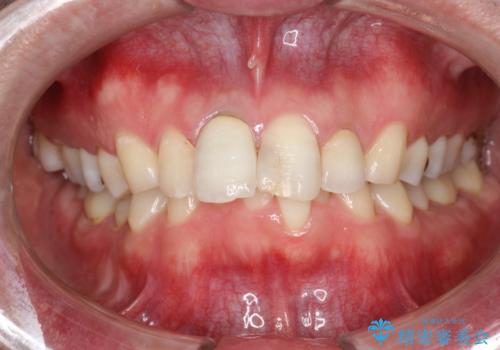

- 約3年ほど歯科医院での定期健診やクリーニングを受けてないとのことでした。全体的に歯石・着色などが付着していていたためPMTC60分コースを行いました。

分厚く歯石や着色が付着していると、汚れなのか虫歯なのかの判別がしづらい場合があります。しばらく定期健診やクリーニングを行っていない場合は、まずはしっかりと汚れを除去し、本来のご自身の歯の状態にすることで、より精密なお口の状態の診断が行えます。

PMTCによって、CRと、ご自身の歯の境目の着色などがしっかりと落とせて目立たなくなる場合と、PMTCによってしっかりとクリーニングを行うと、CR自体が古く劣化・変色などしていて目立ってくる場合があります。気になる際は詰め替えを行います。